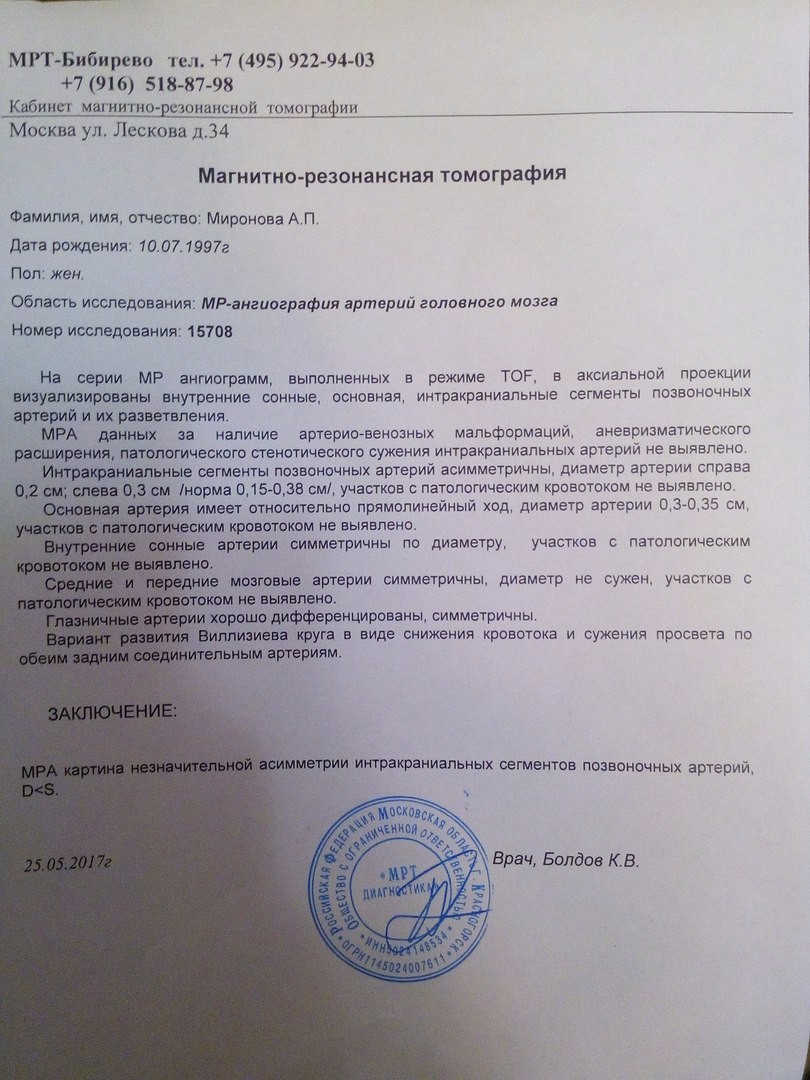

МРТ головного мозга: Расшифровка снимков и Интерпретация

Раздел: Визуальные уроки